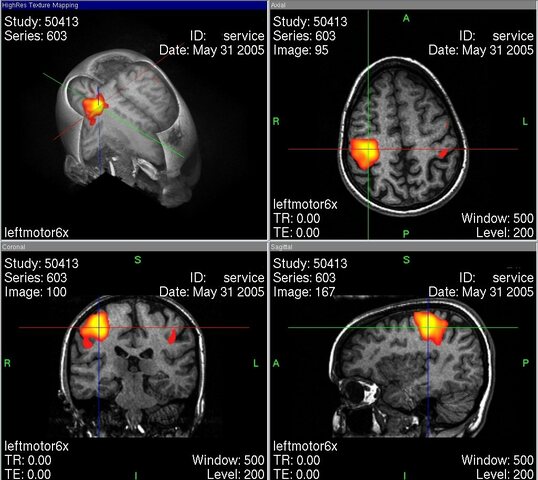

• Imágenes funcionales

Imágenes funcionales

En especial la resonancia magnética y la tomografía por emisión de positrones